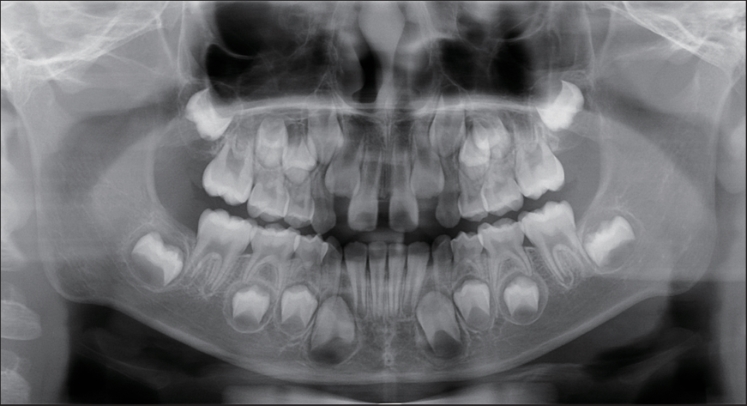

目的 应用口腔全景曲面体层片研究乳尖牙双根的发生率和特征。 方法 收集3~9岁儿童的口腔全景曲面体层片,共纳入100 976张,观察记录乳尖牙双根的发生情况和分布规律。应用SPSS 25.0统计软件分析所得的数据。查阅乳尖牙双根的报道文献,记录患者资料。 结果 乳尖牙双根的发生率为0.37‰(37/100 976),其中男性发生率为0.59‰(32/54 276),女性发生率为0.12‰(5/46 700),男女间差异有统计学意义(χ2 =15.955,P=0.000)。37例儿童的乳尖牙双根发生数目以1~2颗为主,其中1颗者11例(29.73%),2颗者18例(48.65%)。76颗乳尖牙双根的牙位分布左侧和右侧间差异无统计学意义(χ2 =1.316,P=0.251),上颌和下颌间差异有统计学意义(χ2 =15.213,P=0.000),单侧和双侧间差异有统计学意义(χ2 =6.083,P=0.014)。 结论 乳尖牙双根罕见,发生数目多为1~2颗,男性多于女性,上颌多于下颌,双侧发生多于单侧发生。

Objective The incidence and clinical characteristics of bi-rooted primary canines were investigated by performing oral panoramic radiographs. Methods A total of 100 976 oral panoramic radiograph of subjects aged 3-9 years old were collected, and the incidence and distribution of bi-rooted primary canines were observed and recorded. The obtained data were analyzed using SPSS 25.0 statistical software, and the literature on bi-rooted primary canine was reviewed to record patient’s data. Results The incidence of bi-rooted primary canines was 0.37‰ (37/100 976), of which 0.59‰ (32/54 276) occurred in males and 0.12‰ (5/46 700) in females. Statistically significant difference was observed between males and females (χ2 =15.955, P=0.000). The number of bi-rooted primary canine in 37 children was mainly 1-2. Among them, 11 subjects (29.73%) had one bi-rooted primary canine, and 18 subjects (48.65%) had two bi-rooted primary canines. The tooth position distribution of 76 bi-rooted primary canines showed no significant difference between the left and right sides (χ2 =1.316, P=0.251). However, significant difference was found between the upper and lower jaws (χ2 =15.213, P=0.000) and between the unilateral and bilateral sides (χ2 =6.083, P=0.014). Conclusion Bi-rooted primary canines are rare, mostly occur in 1-2 teeth, and are more common in males than females, in the upper jaw than in the lower jaw, and on both sides than on one side.